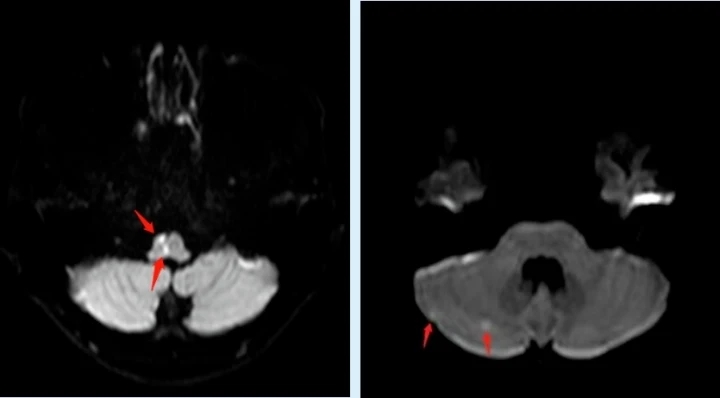

不久前,高三在讀學生小黃在課間休息時突然感覺自己左側肢體麻木、乏力,走路搖搖晃晃的,班主任見狀立即呼叫120送至惠州市第一人民醫院神經內科就診,出乎所有人的意料,平時生活作息規律、飲食均衡、熱愛運動且年僅17歲的小黃竟然得了“中風”!頭顱MR顯示延髓、右側枕葉及右側小腦半球多發腔隙性腦梗死。